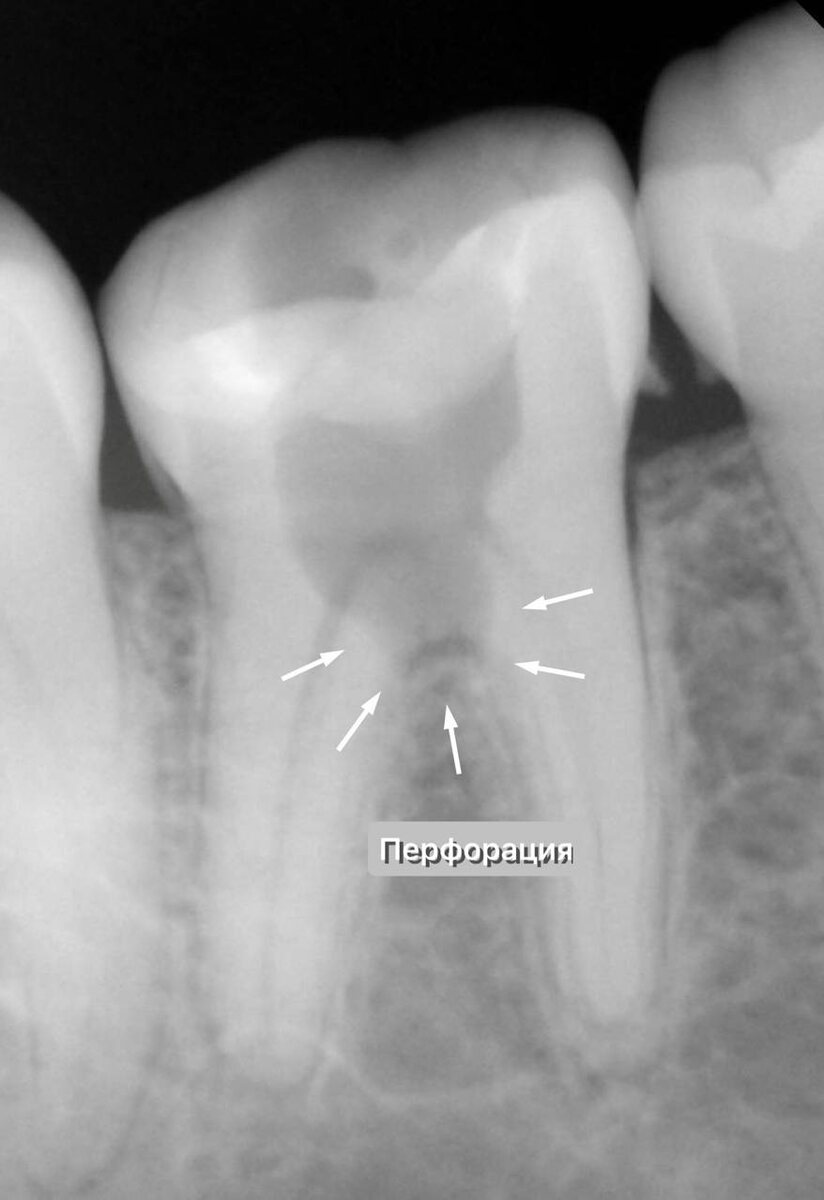

Перфорация дна полости зуба в зоне бифуркации корней

Первым делом выполняем диагностический RG снимок. А там...

Перфорация дна полости зуба в зоне бифуркации

Огромная перфорация дна полости зуба в зоне бифуркации! Между корнями! Зуб пропилили насквозь, о ужас. Создали искусственное отверстие, через которое полость зуба сообщалась с окружающими тканями.

Это очень и очень плохо. Но самое страшное открытие ждало после снятия временной пломбы.